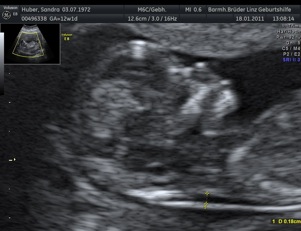

Neben den ganz normalen MUKIPA-Untersuchungen liegt der Schwerpunkt der gynäkologischen Wahlarztpraxis in der Ultraschalldiagnostik,

d.h. pränataler Ultraschall (Messung der Nackendicke, Organscreening) einerseits, andererseits kann noch eine Untersuchung mittels 4D-Ultraschall durchgeführt werden,

wo ein dreidimensionales Bild von Ihrem Kind angefertigt werden kann.

Dieses ermöglicht die Diagnostik einiger Fehlbildungen wie etwa der Lippen-Kiefer-Gaumenspalte, andererseits kann so das erste "Foto" von Ihrem noch ungeborenen Kind gemacht werden, was die Mutter-Kind-Beziehung zusätzlich fördert.